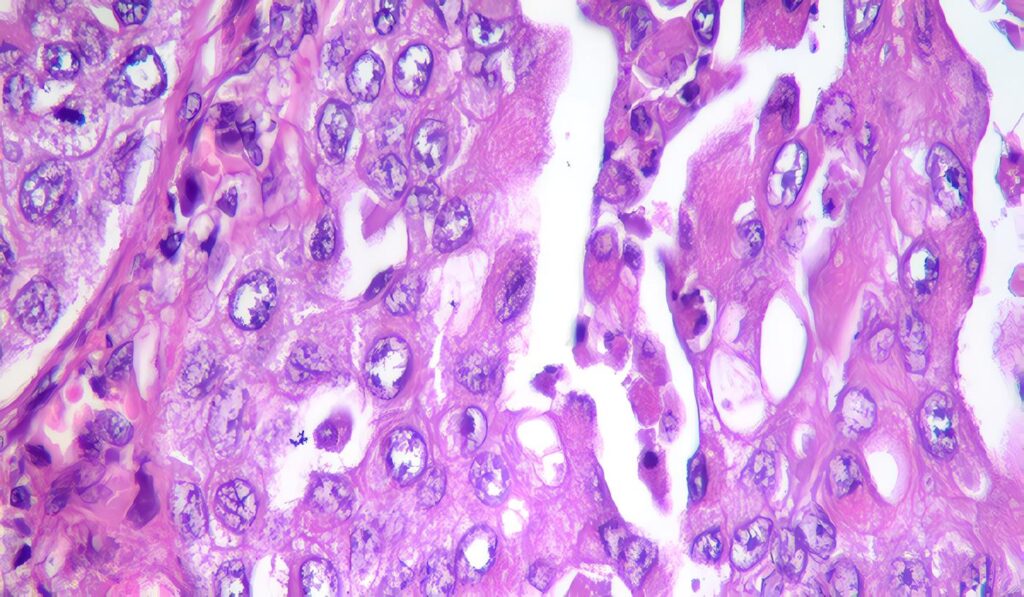

Carcinoma de Células Transicionales localizado en el Tracto Urinario Superior

Artículos de Revisión Manejo Uteroscópico del Carcinoma de Células Transicionales localizado en el Tracto Urinario Superior Evidencia Hoy Juan Guillermo...

Manejo Endoscópico del CCT

Tratamiento Las principales indicaciones para manejo endoscópico del CCT de localización en el TUS son: Asociado a insuficiencia renal, Paciente...